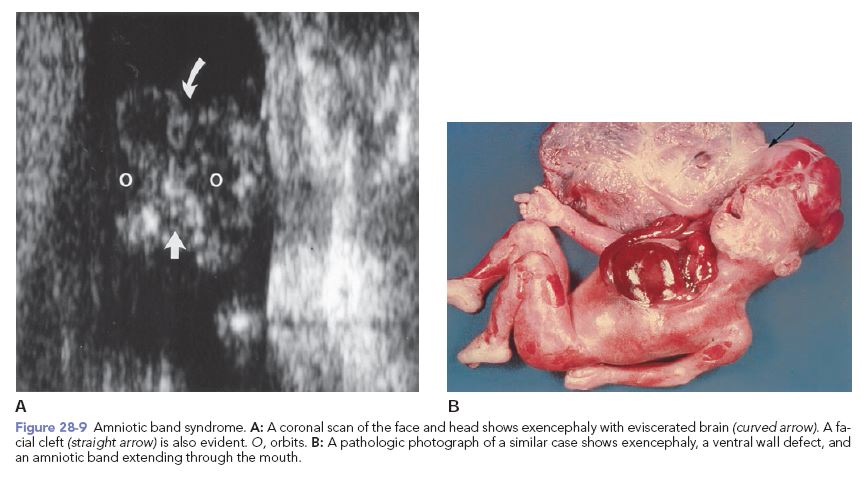

Amniotic band syndrome, also known as constriction ring syndrome, happens when fibrous bands of the amniotic sac (the lining inside the uterus that contains a fetus) get tangled around a developing fetus.

In rare cases, the bands wrap around the fetus’ head or umbilical cord. Most of the time, the bands wrap around an arm, leg, fingers, or toes. This can cause serious constrictions (tightening), acting like a tight rubber band around the body part. Most children with amniotic band syndrome will have bands on more than one part of the body.

Some children with amniotic band syndrome may also have cleft lip and/or cleft palate. Children with amniotic band syndrome often also have clubfoot.

Amniotic band syndrome is sometimes diagnosed before birth with an ultrasound test. Most of the time, it is seen when a baby is born. Your child may have an x-ray to help find out how serious the problem is.